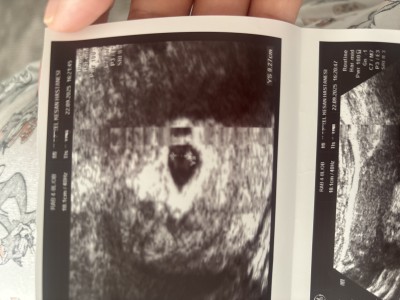

22 Eylül’de doktor randevum vardı yani pazartesi günü dün. doktor betaya göre ve haftama göre kesenin küçük olduğunu söyledi kese 0,82cm yazıyor ultrason kâğıdında. Bir önceki sorum da bu detayları vermemiştim o yüzden tekrar soruyorum lütfen bu haftalarda ya da bu beta değerinde Sizde durumlar nasıldı ya da çevrenizde böyle olup da normal gebeliğe devam eden oldu mu Fotoğrafta paylaşacağım lütfen bakar mısınız. Normalde 5 + 2 Haftalıkken ultrasonda 4 + 6 Görünüyor. Beni tedirgin eden doktorun kesenin çok ufak olduğunu söylemesi betaya göre

Gebelik haftası 5+3